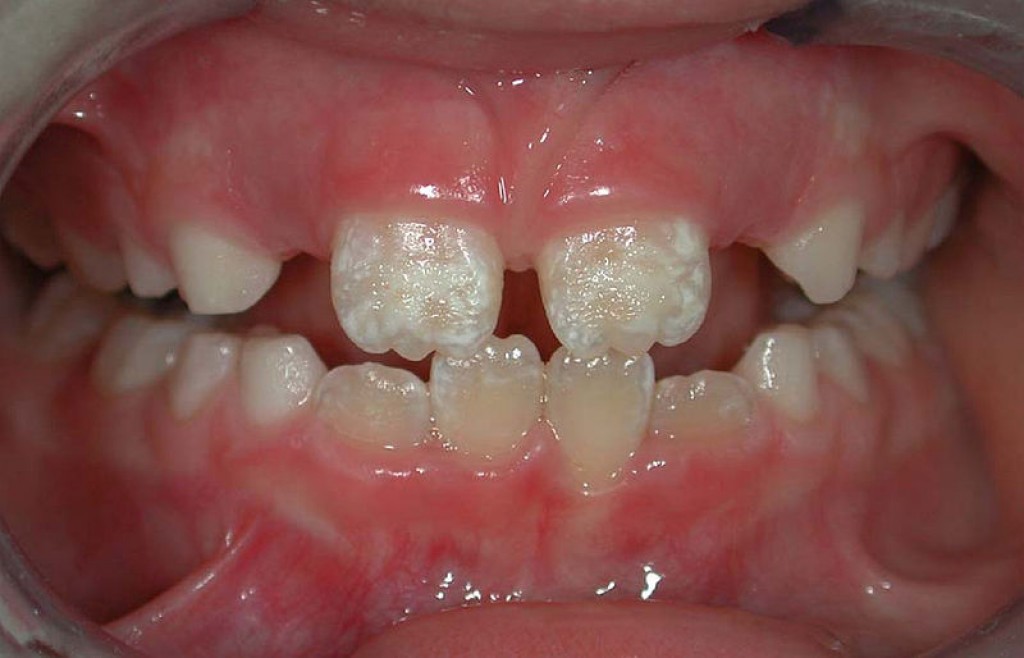

حاج آقایی// برخی داروها باعث نقص مینای دندان کودکان می‌شوندبه گزارش خبرگزاری صدا و سیما؛ حدود ۲۰ درصد از کودکان در سراسر جهان دچار این نقایص هستند که تأثیر چشمگیری بر سلامت و ظاهر دندان آن‌ها دارد. نقص مینای دندان‌ها نوعی ناهنجاری است که بر ساختار و یکپارچگی مینا (لایه بیرونی سخت و محافظ دندان) تأثیر می‌گذارد. این نقص ممکن است مادرزادی یا اکتسابی باشد. نقص مینای دندان با ضعف یا گچی بودن مینا و کم بودن ضخامت یا کیفیت آن مشخص می‌شود.

در سال‌های اخیر، دندانپزشکان متوجه افزایش شدید تعداد کودکانی شده اند که به دنبال درمان درد، لکه‌های سفید یا زرد روی دندان‌ها، حساسیت دندانی و... هستند. آن‌ها دریافتند در برخی موارد، جویدن ساده باعث شکستگی دندان‌های کودکان می‌شود. همه این مشکلات علایم معمول نوعی نقص مینای دندان است که به‌عنوان هیپومینرالیزاسیون مینای دندان شناخته می‌شود و دلیل ایجاد آن به‌خوبی شناخته نشده است.

کسانی که دچار این اختلال هستند، زودتر و بیشتر دچار پوسیدگی دندان می‌شوند و احتمال شکستن دندان‌های آن‌ها بیشتر است. پژوهش‌ها نشان داده‌اند که ممکن است آن‌ها ۱۰ برابر بیشتر از افراد دارای دندان‌های سالم در طول زندگی خود مجبور به ترمیم دندان‌هایشان شوند.